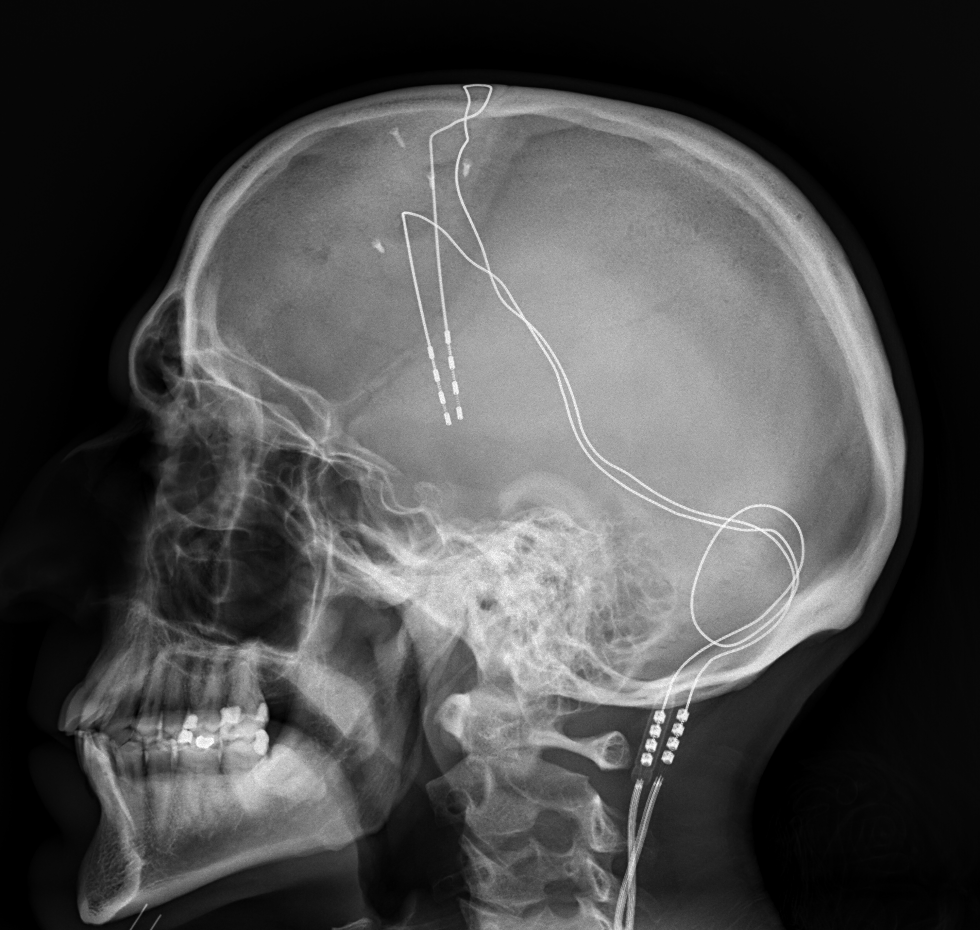

LSAP Cadmus-Aram深层大脑梦境顶叶刺激阵列。

除此之外,O5-1征用了LSAP Cadmus-Aram深层大脑梦境顶叶刺激阵列,一种由Hadley Cadmus博士和Robert Aram博士在后者仍受聘于基金会超常科技部时构建的原型机,仅此一台。该设备由两个独立部件组成——一件医学植入物,包含数个插入脑组织的电极,引出一根通过后颈的金属线;一套与金属线连接的计算机化系统。植入物会刺激脑组织,在做梦过程中产生一种高度意识状态,而计算机将记录感知和视觉图像,并生成对应文本。文本需额外人工处理,但其最终产物为对象言行基本准确的抄录,包括其梦中言行。

该设备此前由心灵致动部门测试,并确认其使用安全。设备被植入Lucian Greaves中尉,以按照O5法令#2050对行动中的发现进行确凿公正的记录供议会作证。接受手术并于Site-12度过了两周的康复期后,Greaves返回MKF-01准备于2002年12月20日第一次尝试通过灵魂投射进入玛珠。